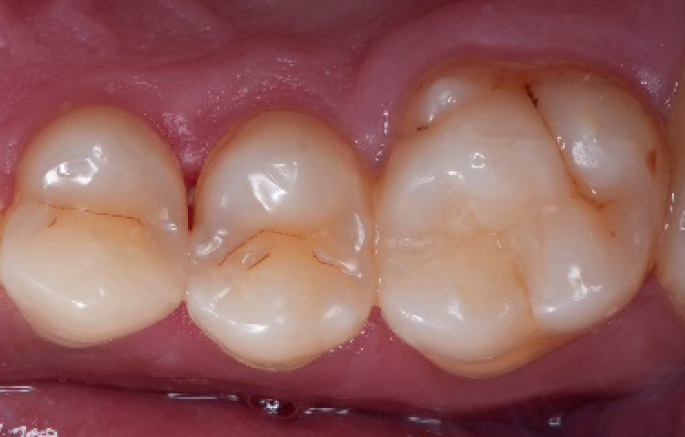

Initial situation of the patient

The patient came for a routine control appointment. She didn‘t report any symptoms but some bleeding during brushing.

Initial situation: an old class I composite restoration on 1.6. New caries on the mesial wall. Presence of plaque and inflammation.